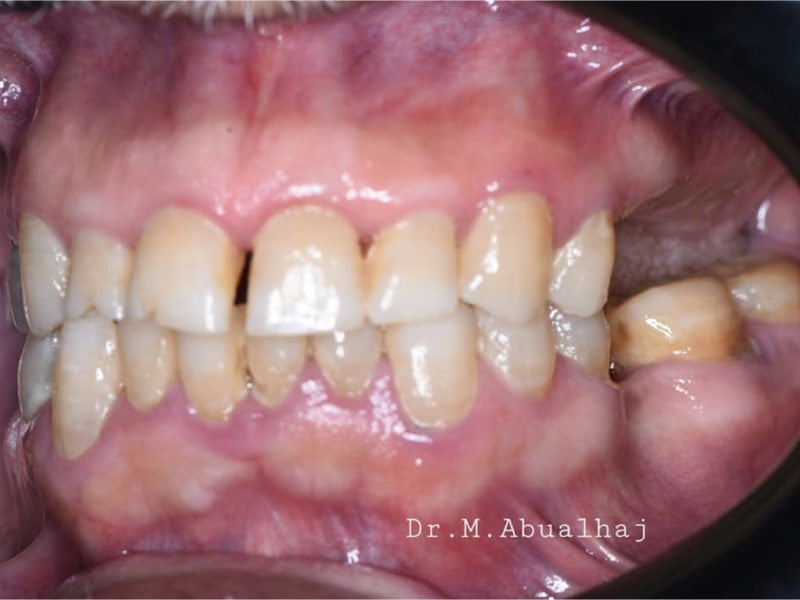

Patient's Data:

- Age: 51

- Sex: Female

- Smoker: No

- Pathologies: None

- Hygenic state: Good

- Alergies: None

In this case we used the implant cap to model the peek healing screw and obtain a different gingival profile more suitable for the implant site.